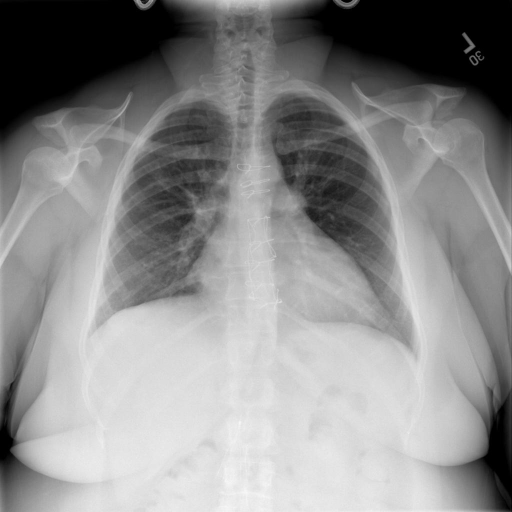

# 本文贡献 ![](./assets/images/xrayglm.png) - 借助ChatGPT以及公开的数据集,我们构造了一个`X光影像-诊断报告`对的医学多模态数据集; - 我们将构建的中文胸部X光片诊断数据集在[VisualGLM-6B](https://github.com/THUDM/VisualGLM-6B)进行微调训练,并开放了部分训练权重用于学术研究; # 数据集 - [MIMIC-CXR](https://physionet.org/content/mimic-cxr-jpg/2.0.0/)是一个公开可用的胸部X光片数据集,包括377,110张图像和227,827个相关报告。 - [OpenI](https://openi.nlm.nih.gov/faq#collection)是一个来自印第安纳大学医院的胸部X光片数据集,包括6,459张图像和3,955个报告。 在上述工作中,报告信息都为非结构化的,不利于科学研究。为了生成合理的医学报告,我们对两个数据集进行了预处理,并最终得到了可以用于训练的**英文报告**。除此之外,为了更好的支持中文社区发展,借助ChatGPT的能力,我们将英文报告进行了中文翻译,并最终形成了可用于训练的数据集。 |数据集|数量|下载链接| |:-|:-|:-| |MIMIC-CXR-zh|-|-| |OpenI-zh|6,423|[诊疗报告](./data/Xray/openi-zh.json) 、[X光影像](https://pan.baidu.com/s/13GBsDMKf6xBZBSHpoWH_EA?pwd=k9sh)| # 快速上手 1. 安装环境 ```bash # 安装依赖 pip install -r requirements.txt # 国内换源安装依赖 pip install -i https://mirrors.aliyun.com/pypi/simple/ -r requirements.txt ``` 此时默认会安装`deepspeed`库(支持`sat`库训练),此库对于模型推理并非必要,同时部分`Windows`环境安装此库时会遇到问题。 如果想绕过`deepspeed`安装,我们可以将命令改为: ```bash # 安装依赖 pip install -i https://mirrors.aliyun.com/pypi/simple/ -r requirements_wo_ds.txt # 安装SwissArmyTransformer pip install -i https://mirrors.aliyun.com/pypi/simple/ --no-deps "SwissArmyTransformer>=0.3.6" ``` 2. 模型推理 CLI推理: ```python python cli_demo.py --from_pretrained checkpoints/finetune-XrayGLM-05-25-01-04 --prompt_zh '详细描述这张胸部X光片的诊断结果' ``` 更多[参数](https://github.com/WangRongsheng/XrayGLM/blob/main/cli_demo.py#L16) # 效果展示 诊断: |X光影像|诊疗报告(医生)|XrayGLM| |:-|:-|:-| |![](./data/Xray/2_1.png)|根据X射线图像,心脏大小正常,肺部看起来很清晰。已经排除了肺炎、积液、水肿、气胸、腺病、结节或肿块的存在。该发现表明一切正常。换句话说,总体印象是胸部正常。|X光片显示,心脏大小正常。肺部没有气胸或胸腔积液的证据。骨骼结构看起来没有任何异常。总的来说,X光片表明没有发现急性心肺疾病的迹象。| |![](./data/Xray/2882_1.png)|X光图片显示没有扭曲的区域、可疑的骨质不透明度或胸腺积液。心脏大小轻微增大,但非常稳定。此外,没有气胸的证据,肺野也正常。总体来说,X光片显示没有急性心脏异常,但要注意轻微的心脏扩大。|X光片显示,心脏大小正常。肺部和纵隔轮廓清晰,没有气胸或胸腔积液的证据。骨骼结构完整,没有任何急性异常。| |![](./data/Xray/2577_1.png)|心影形态在正常范围内。没有急性骨质异常。有可能出现没有明显的吸水或肺实质状况的线索。没有大面积积液或气胸。有可能怀疑其有误吸或肺实质问题。为了确诊和治疗,可能需要进行适当的影像学随访。|心脏大小正常,肺部和纵隔轮廓清晰。没有急性异常或活动受限的证据。没有任何明显的气胸、胸腔积液或肺不张的迹象。此外,也没有发现任何局灶性骨质异常或其他急性疾病。| 多轮对话: |X光影像|诊疗报告(医生)| |:-|:-| |![](./data/Xray/861_1.png)|右侧主动脉突出观察到。心脏大小正常。胸部未发现明显的肺气肿、胸膜积液或可疑的肺部病变。报告指出已知右侧主动脉情况正常。| ```bash >> X光影像路径:./data/Xray/861_1.png >> 用户:这是一张什么图? >> XrayGLM:这张图片显示的是一张肺部检查的X光片。 >> 用户:请描述这张胸部X光片的诊断结果 >> XrayGLM:心脏大小正常,肺部清晰。没有急性心肺疾病的证据。 >> 用户:是否存在肺气肿? >> XrayGLM:没有肺气肿。心脏大小正常,肺部清晰。没有发现急性心肺疾病的证据。 >> 用户:平时饮食该注意什么? >> XrayGLM:饮食应该健康,均衡。建议增加蛋白质的摄入量,因为蛋白质有助于维持肌肉和骨骼的健康。多食用蔬菜、水果、全谷物以及健康的脂肪来源如橄榄油、鱼类等可以帮助获得足够的维生素和矿物质。此外,避免过度饮酒或吸烟,这些习惯可能会对心脏健康产生负面影响。 ``` # 项目致谢 1. [VisualGLM-6B](https://github.com/THUDM/VisualGLM-6B)为我们提供了基础的代码参考和实现; 2. [MiniGPT-4](https://github.com/Vision-CAIR/MiniGPT-4)为我们这个项目提供了研发思路; 3. ChatGPT生成了高质量的中文版X光检查报告以支持XrayGLM训练; 4. [gpt_academic](https://github.com/binary-husky/gpt_academic)为文档翻译提供了多线程加速; 5. [MedCLIP](https://github.com/RyanWangZf/MedCLIP) 、[BLIP2](https://huggingface.co/docs/transformers/main/model_doc/blip-2) 、[XrayGPT](https://github.com/mbzuai-oryx/XrayGPT) 等工作也有重大的参考意义; ![](./assets/images/mpu.png) 这项工作由[澳门理工大学应用科学学院](https://www.mpu.edu.mo/esca/zh/index.php)硕士生[王荣胜](https://github.com/WangRongsheng) 、[段耀菲](https://github.com/IsBaSO4) 、[李俊蓉](https://github.com/lijunrong0815)完成,指导老师为檀韬副教授、[彭祥佑](http://www.patrickpang.net/)老师。 *特别鸣谢:[USTC-PhD Yongle Luo](https://github.com/kaixindelele) 提供了有3000美金的OpenAI账号,帮助我们完成大量的X光报告翻译工作 # 免责声明 本项目相关资源仅供学术研究之用,严禁用于商业用途。使用涉及第三方代码的部分时,请严格遵循相应的开源协议。模型生成的内容受模型计算、随机性和量化精度损失等因素影响,本项目无法对其准确性作出保证。即使本项目模型输出符合医学事实,也不能被用作实际医学诊断的依据。对于模型输出的任何内容,本项目不承担任何法律责任,亦不对因使用相关资源和输出结果而可能产生的任何损失承担责任。 # 项目引用 如果你使用了本项目的模型,数据或者代码,请声明引用: ```bash @misc{wang2023XrayGLM, title={XrayGLM: The first Chinese Medical Multimodal Model that Chest Radiographs Summarization}, author={Rongsheng Wang, Yaofei Duan, Junrong Li, Patrick Pang and Tao Tan}, year={2023}, publisher = {GitHub}, journal = {GitHub repository}, howpublished = {\url{https://github.com/WangRongsheng/XrayGLM}}, } ``` # 使用许可 此存储库遵循[CC BY-NC-SA](https://creativecommons.org/licenses/by-nc-sa/4.0/) ,请参阅许可条款。